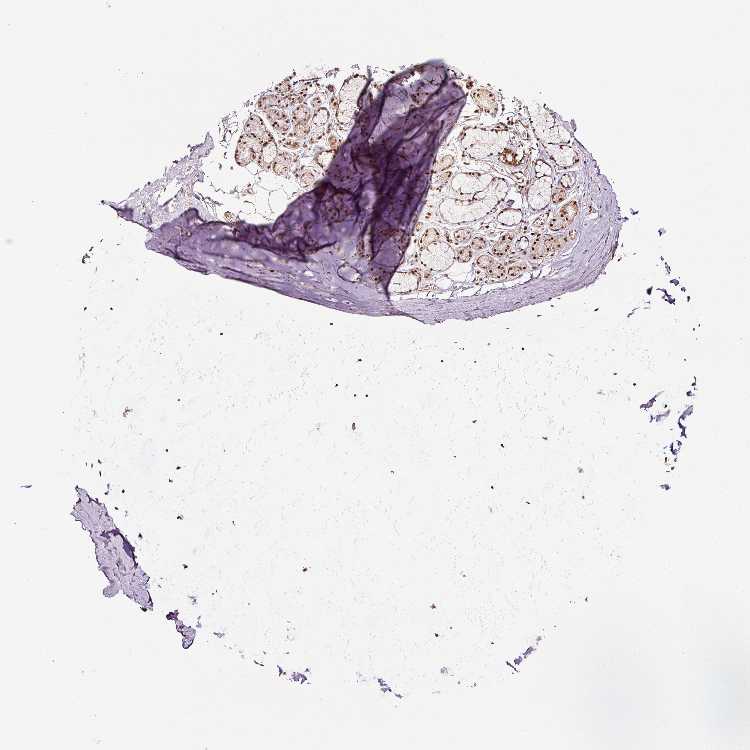

ADIPOSE TISSUE - Antibody stainingi

Antibody staining in the annotated cell types in the current human tissue is reported as not detected, low, medium, or high, based on conventional immunohistochemistry profiling in selected tissues. This score is based on the combination of the staining intensity and fraction of stained cells.

Each image is clickable and will lead to virtual microscopy that enables deeper exploration of all samples and also displays staining intensity scores, fraction scores and subcellular localization as well as patient and tissue information for each sample.

Antibody HPA049123Antibody HPA058507Antibody CAB004557

Adipocytes LowNot detectedMedium